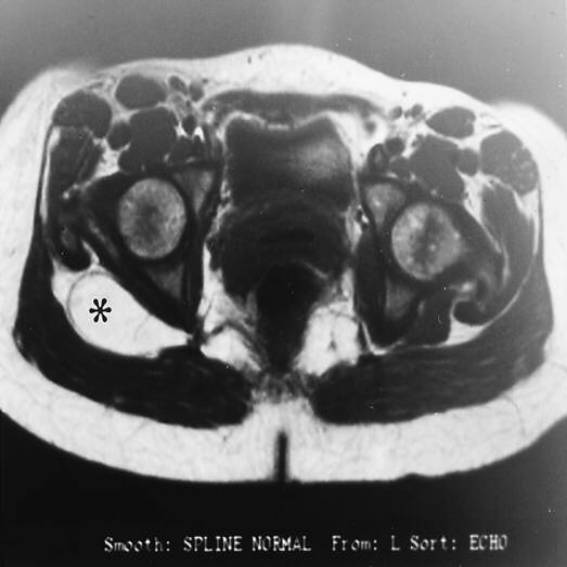

La resonancia magnética es la técnica de elección para definir la anatomía de los tumores del tejido blando. En base a los signos características, varias lesiones --los lipomas, hemangiomas, y gangliones-- puede diagnosticarse con precisión con un grado alto y fiable de especificidad.

Los lipomas tienen signos característicos que son exactamente idénticas a la grasa hipodérmica en todas las secuencias. Puede haber áreas pequeñas de cordones fibrosos. Los lipomas se demarcan bien y no invaden o penetran los límites de la fascia. No tienen el modelo de crecimiento centrípeto de los sarcomas y a menudo forman apéndices o áreas irregularmente formadas en dónde comprimen los planos intermuscular  o el espacio adventicial (Figura 1A y 1B).